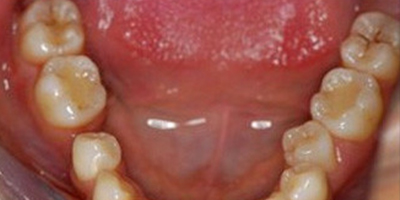

適宜人群 牙齒疼痛、牙齦出血、牙齦紅腫、牙周炎。

治療時間短,效果顯著,能有效緩解牙周炎。

適用人群有限。